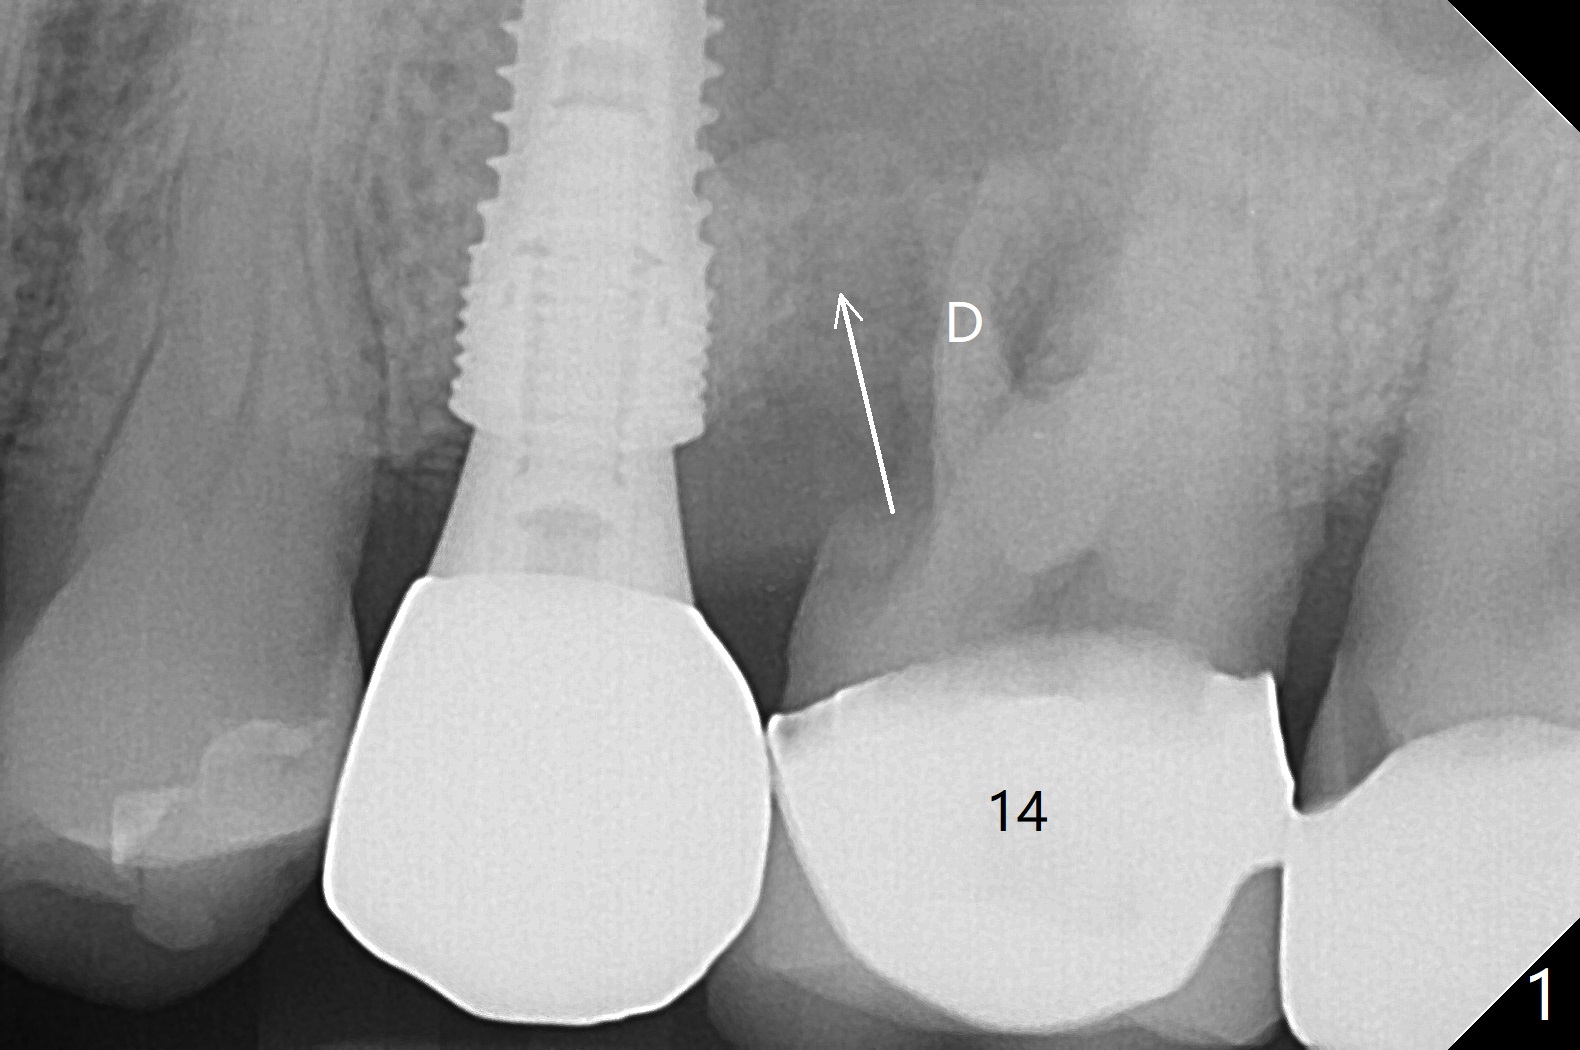

The vertical mesiobuccal root fracture of #14 of a 59-year-old man has become worse in the last 10 months. The mesial portion appears to be separate and have migrated mesiobuccal from its original place (Fig.1,2). CT taken 10 months earlier shows that the septal bone seems to be thin (Fig.3). Use IS drills (pointed to 3 mm in diameter) with 2 or 3 mm stoppers to start osteotomy and Magic Sinus Lifter. Place a 4.5x9 mm FC. If the latter fails, use sticky bone for sinus lift and socket preservation, followed PRF membranes (3-4), Cytoplast (small piece, smaller than the wound) and setting acrylic to close the sockets, including buccal defect. Take new CT (5x5) for update.